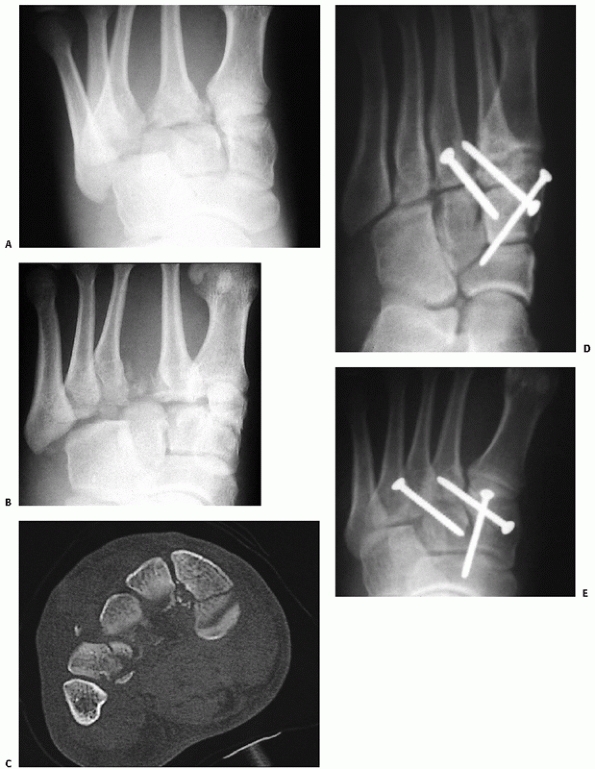

![]() |

FIGURE 60-7 Displaced closed navicular fracture. A,B. Anteroposterior and lateral films of comminuted fracture of the navicular with disruption of the articular body. C. Preoperative CT scan showing extent of injury to navicular. D,E. Postoperative anteroposterior and lateral with navicular reduced and stabilized with two 3.5-mm lag screws.